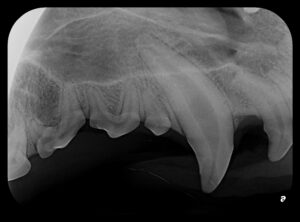

Our team uses state-of-the-art diagnostics and gentle techniques to ensure your pet’s comfort throughout treatment. Before-and-after photos illustrate the clinical and radiographic results of a successful canine tooth root canal, showing how we can preserve and restore teeth to full function.